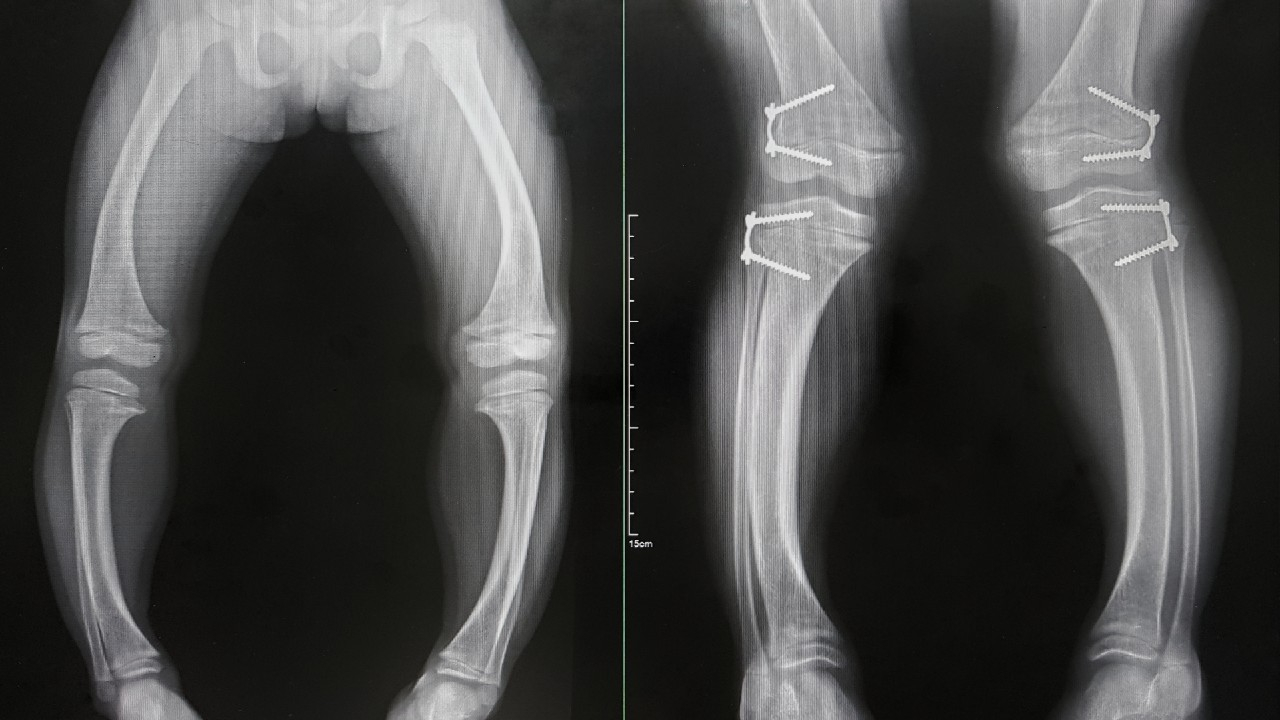

Rachitas – kaulų ir raumenų liga, sukelianti kaulų minkštėjimą ir deformacijas.

Rachitas yra lėtinė kaulų ir raumenų liga, kurią sukelia kaulų mineralizacijos sutrikimai. Dėl to kaulai tampa minkšti, silpni ir linkę deformuotis.

Liga dažniausiai pasireiškia vaikams, kai kaulai dar aktyviai auga ir vystosi. Rachitas gali sukelti kaulų augimo sulėtėjimą, netaisyklingą kaulų formą, raumenų silpnumą ir pusiausvyros sutrikimus.

3. Rentgeno nuotraukos. Atlikus kaulų rentgeno tyrimą galima nustatyti kaulų deformacijas, mineralizacijos sutrikimus ir kitas rachito požymius.

Pirmiausia atsiranda kaulų deformacijos – kojos gali tapti kreivos, krūtinės ląsta iškrypti, o kaukolė deformuotis. Tokie pakitimai gali sukelti ne tik estetinius, bet ir funkcinio pobūdžio sunkumus. Be to, rachitas sulėtina vaiko augimą ir gali sukelti raumenų silpnumą, todėl mažylis gali prasčiau judėti ir turėti koordinacijos problemų.